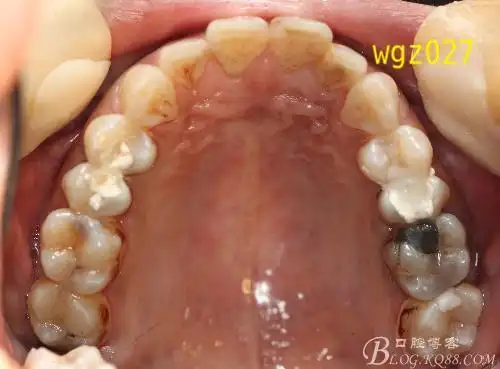

下颌第三磨牙可不可以为正畸利用